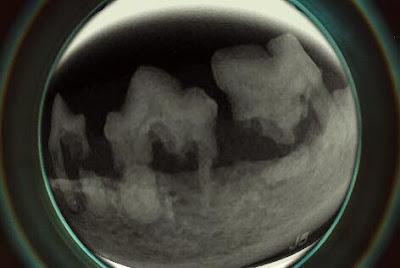

貓咪的牙科問題: 牙齒自我溶解吸收

貓咪的牙齒X光檢查,這些沒有腳的牙齒,

根源於牙齒的自我溶解吸收。常見於貓咪的口炎,需透過牙

科X光才能讓它無所遁形。

這隻貓的牙齒已經保不住了,我們拔掉這些有問題的牙齒來降低口炎的問題。